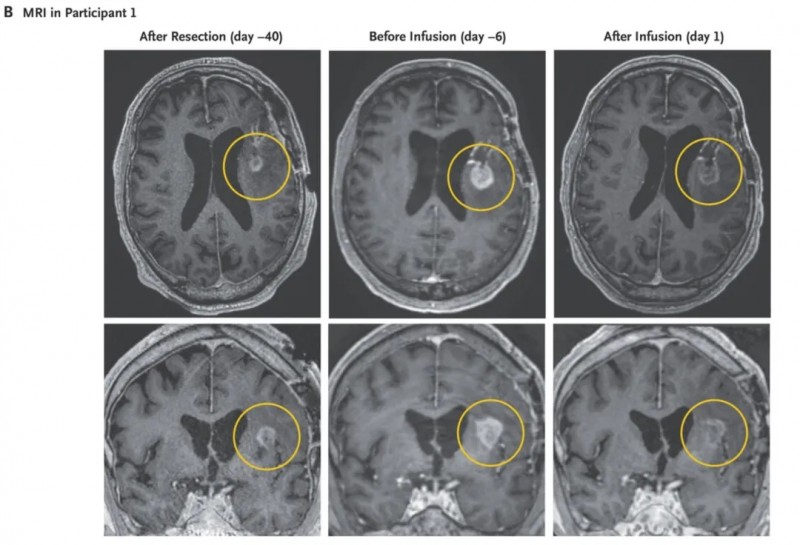

一名74岁男性,因持续1周的头痛、神志不清等症状就诊,后确诊为EGFRvIII阳性胶质母细胞瘤,先后接受过开颅手术、放疗、替莫唑胺化疗等标准治疗效果不佳,MRI提示疾病复发,治疗前6天MRI扫描显示病情活跃进展,之后入组接受CARv3-TEAM-E回输治疗。

1、MRI变化:该患者在单次输注CARv3-TEAM-E后,MRI扫描显示肿瘤快速消退(详见下图),且疗效持续两周。他在第37天接受第2次CARv3-TEAM-ET细胞输注(目前文中暂未报道二次输注后的效果反馈)。

▲图源“NEJM”,版权归原作者所有,如无意中侵犯了知识产权,请联系我们删除